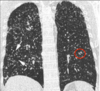

Patrón en panal

Patrón intersticial bibasal